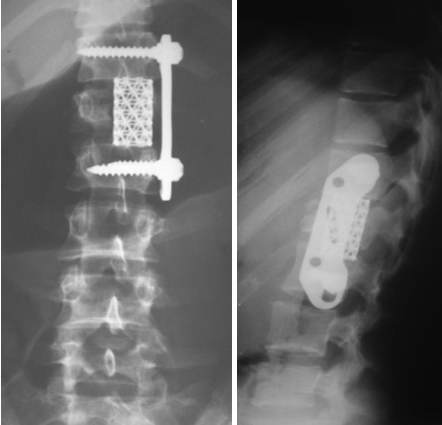

Рентгеновские снимки и медицинские изображения компрессионных переломов